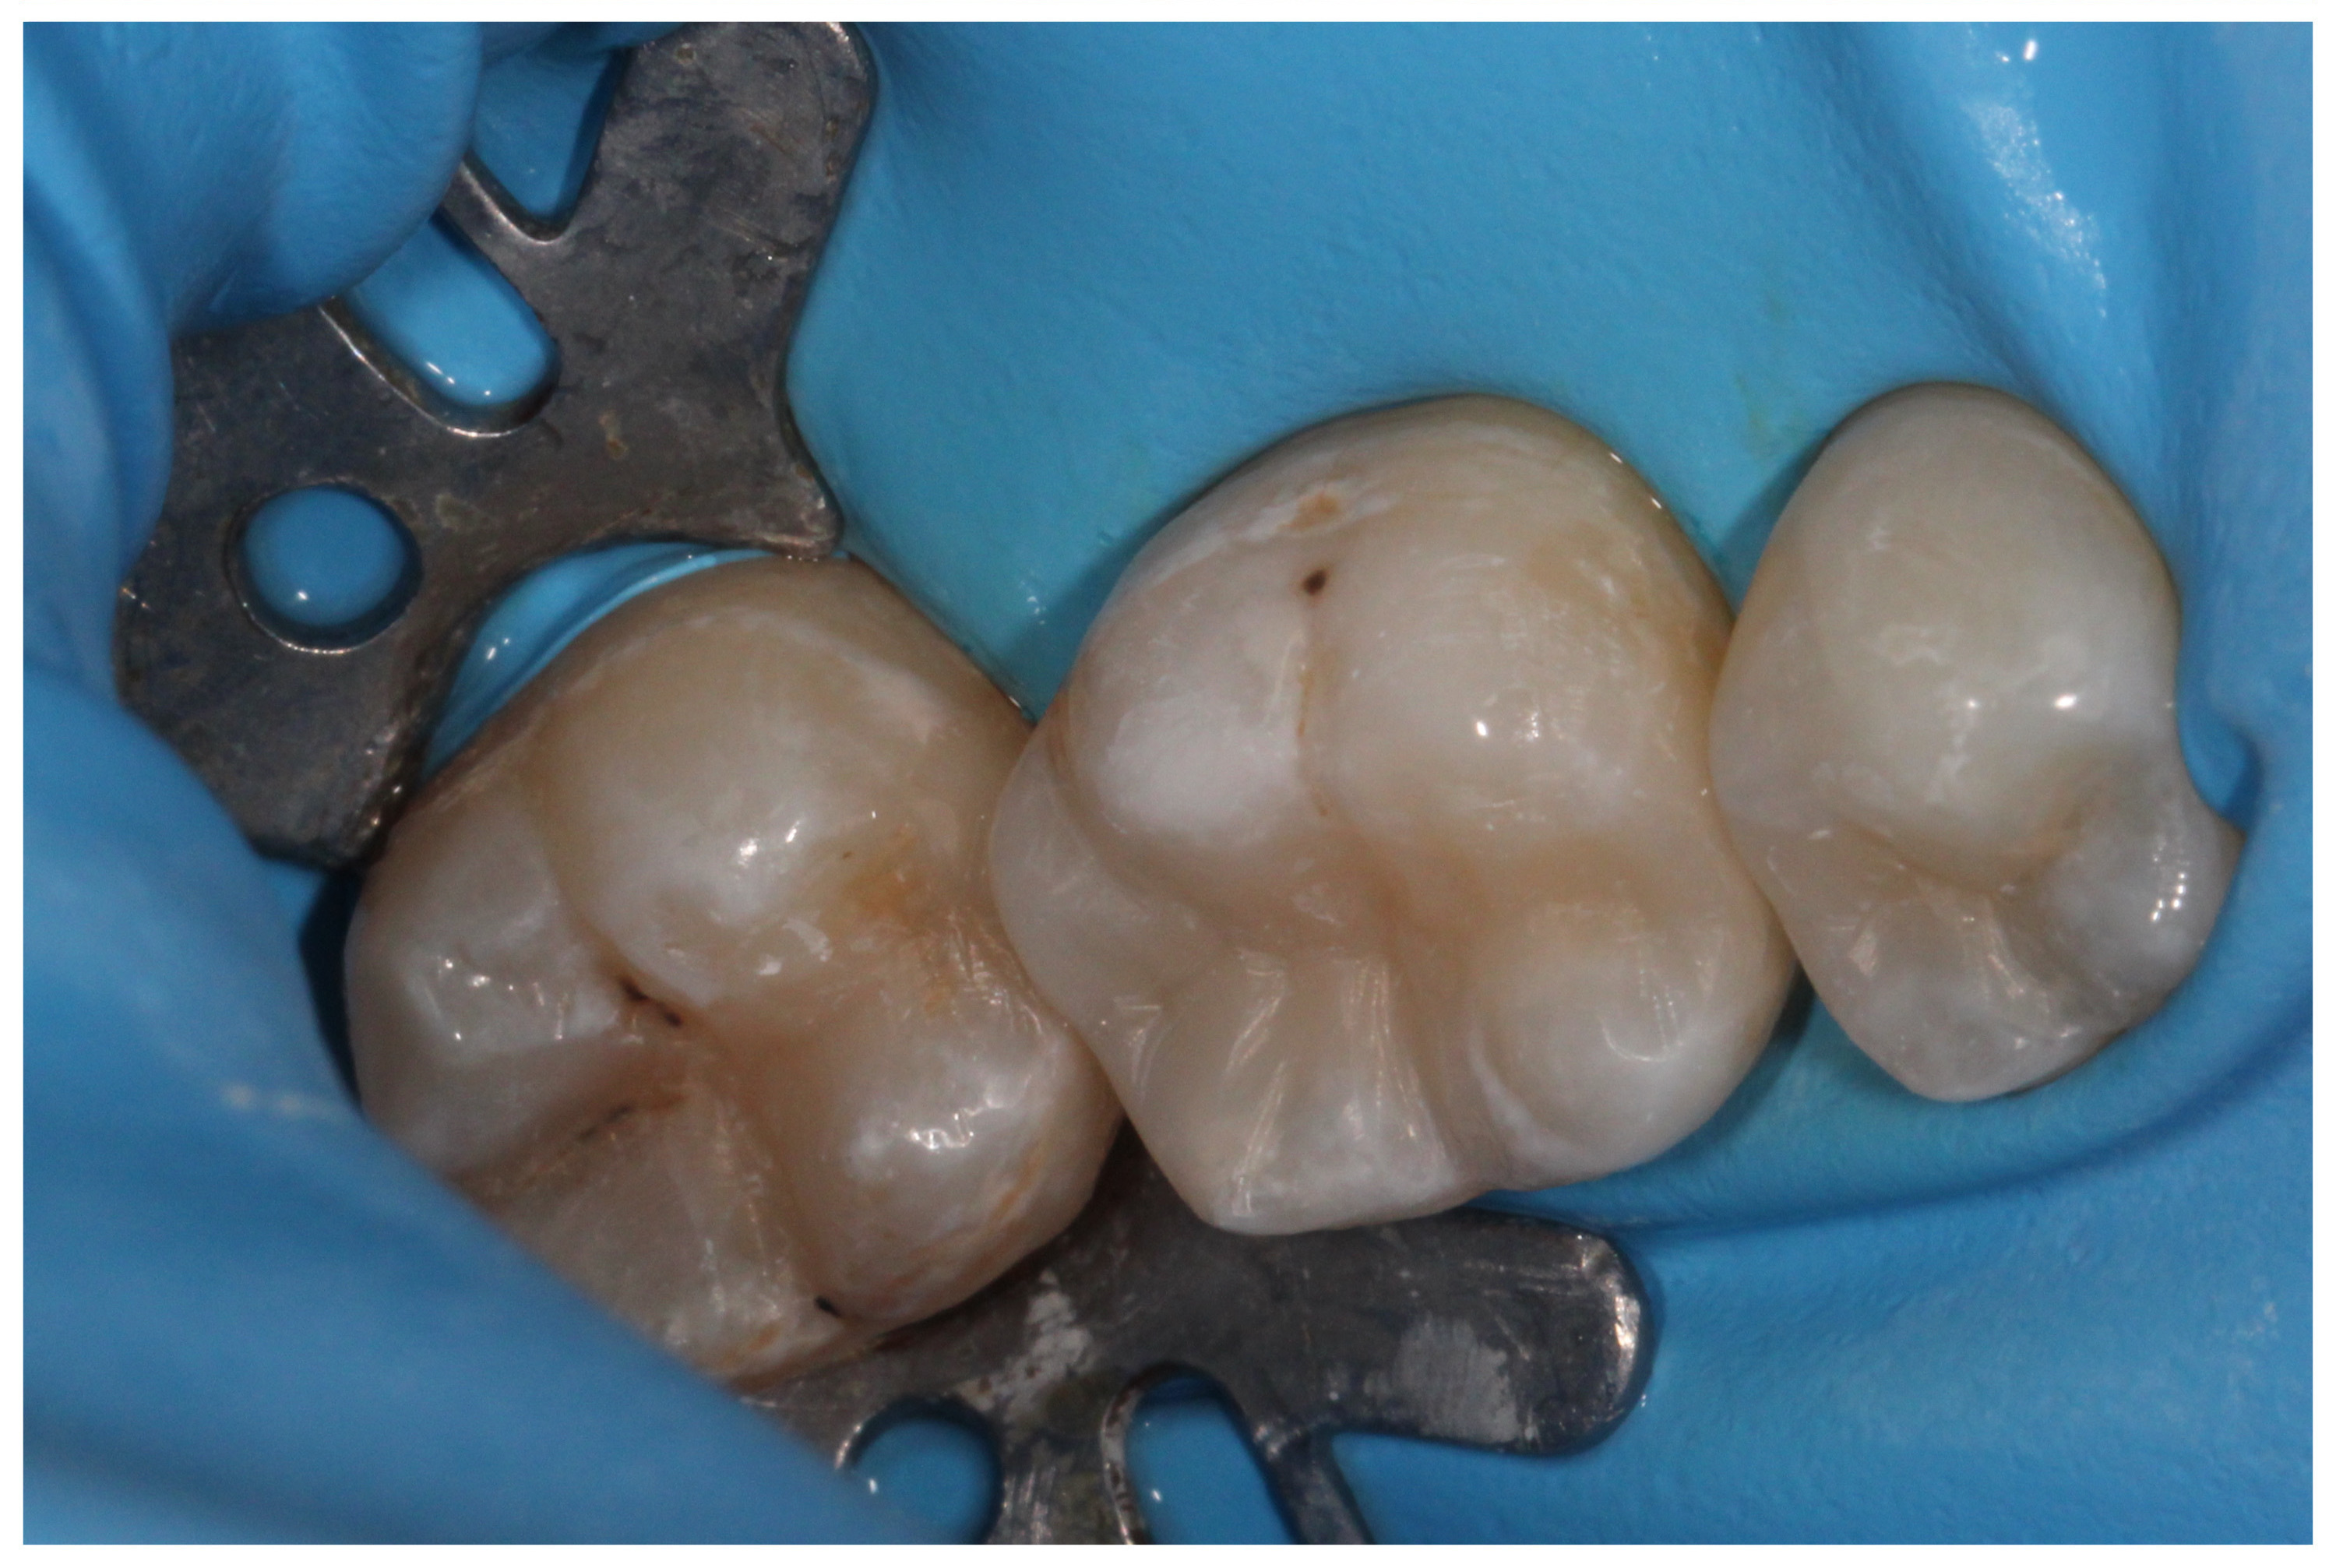

„White“ filling with caries on the first molar, new caries on the second molar

New photocomposite fillings